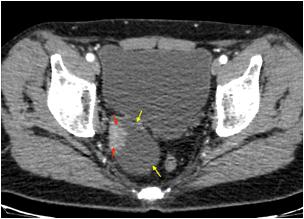

Among the metabolically abnormal patient’s population 20% (n=3) had Hypoglycemia, 40%(n=6) presented with Dyselectrolytemia, 26.67% (n=4) had Uremia, 13.33% (n=2) presented with Hepatic encephalopathy. Overall, 31 patients underwent Lumber puncture, of which CSF report shows abnormality in 11 (35.48%) cases and normal in 20 patients (64.51%). Abnormal CSF report suggesting viral meningoencephalitis found in 46% (n=5), bacterial meningitis in18% (n=2), Tuberculous Meningitis in 27% (n=3), Aseptic meningitis in 9% (n= 1). All 65 subjects underwent CT scan brain among which MRI Brain also done in 55 cases. CT findings is normal in 44.62% (n=29), abnormal in 55.38% (n=36). The most common CNS lesion on CT scan was infarction in 10.77% followed by ring lesion in 9.23% and intracerebral Hemorrhage in 7.96%. We observed cerebral infarction is causative factor of Seizure in female (15%) but intracerebral hemorrhage and ring lesion are most common findings in male, comprising 11.11% patients at each category. The CT scan in new onset Seizure of elderly patient population revealed Infarction in 28.57%, Gliosis in 19.04% and cerebral atrophy in 14.28%. The breakup of findings in MRI Scan of 55 patients shows Hyperintensities on T2, indicating Demyelination / Inflammation/edema in12.31% followed by infarction in 10.77% and ring lesion in 9.23%. In the female population, hyperintensities on T2 MRI found in 15% and Infarction in 15% whereas among the males intracerebral Hemorrhage, Ring lesion and hyperintensities on T2 found at similar occurrence rate @11% in each of these three types of lesions. EEG was done on 80% patients (n=52) of whom 22 patients has abnormal discharge in EEG but 30 patients have normal presentation. Among 65 patients one female expired due to Acute Demyelinated Encephalomyelitis (ADEM) and two males expired one due to Hemorrhage, another one with CNS infection when undergoing treatment indoor.

We found a strong positive correlation between abnormal EEG and abnormal Neuroimaging with Correlation coefficient of 0.902, (P- Value 0.0138) but almost no correlation found between normal EEG with normal Neuroimaging (Figs 1-4).

About 23% of patients with adult onset first seizure has metabolic derangement and the most common etiology was Dyselectrolytemia. The most common Central Nervous System (CNS) Infection as detected by CSF study was viral meningoencephalitis followed by Tuberculous Meningitis. The most common CNS lesion detected by CT studies as well as by MRI Brain was infarction and ring lesion, the two Neuroimaging studies corroborated in 75.38% of Seizure patients. Abnormal discharge in EEG found in34% cases. In majority patients EEG report was normal. EEG abnormality was more common in patients with Focal Seizure rather than GTCS patients. Thus, the most common etiology of first Seizure onset at adult age over 18 years were metabolic derangements (16.92%), CNS Infection or Inflammation (15.38%) and intracerebral Space occupying lesion (15.38%), usually ring lesion, tumors and Metastasis. Idiopathic Seizure found in 7.69% patients. The Correlation between abnormal Neuroimaging and abnormal EEG is strongly positive and statistically significant (P -Value = 0.013) but the same is not true in cases of normal Neuroimaging and normal EEG findings.